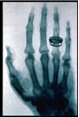

По этой причине Рентген не знал о сделанных до него открытиях и открыл лучи, названные впоследствие его именем, независимо - при наблюдении флюоресценции, возникающей при работе катодолучевой трубки. Рентген занимался Х-лучами немногим более года (с 8 ноября 1895 года по март 1897 года) и опубликовал о них всего три сравнительно небольших статьи, но в них было дано столь исчерпывающее описание новых лучей, что сотни работ его последователей, опубликованных затем на протяжении 12 лет, не могли ни прибавить, ни изменить ничего существенного. Рентген, потерявший интерес к Х-лучам, говорил своим коллегам: "Я уже всё написал, не тратьте зря время". Свой вклад в известность Рентгена внесла также знаменитая фотография руки его жены, которую он опубликовал в своей статье (см. изображение справа). Подобная слава принесла Рентгену в 1901 году первую Нобелевскую премию по физике, причём нобелевский комитет подчёркивал практическую важность его открытия. В 1896 году впервые было употреблено название "рентгеновские лучи". В некоторых странах осталось старое название - X-лучи. В России лучи стали называть "рентгеновскими" с подачи ученика В.К. Рентгена - Абрама Фёдоровича Иоффе.

(Рентгеновская фотография (рентгенограмма) руки своей жены, сделанная В.К. Рентгеном)